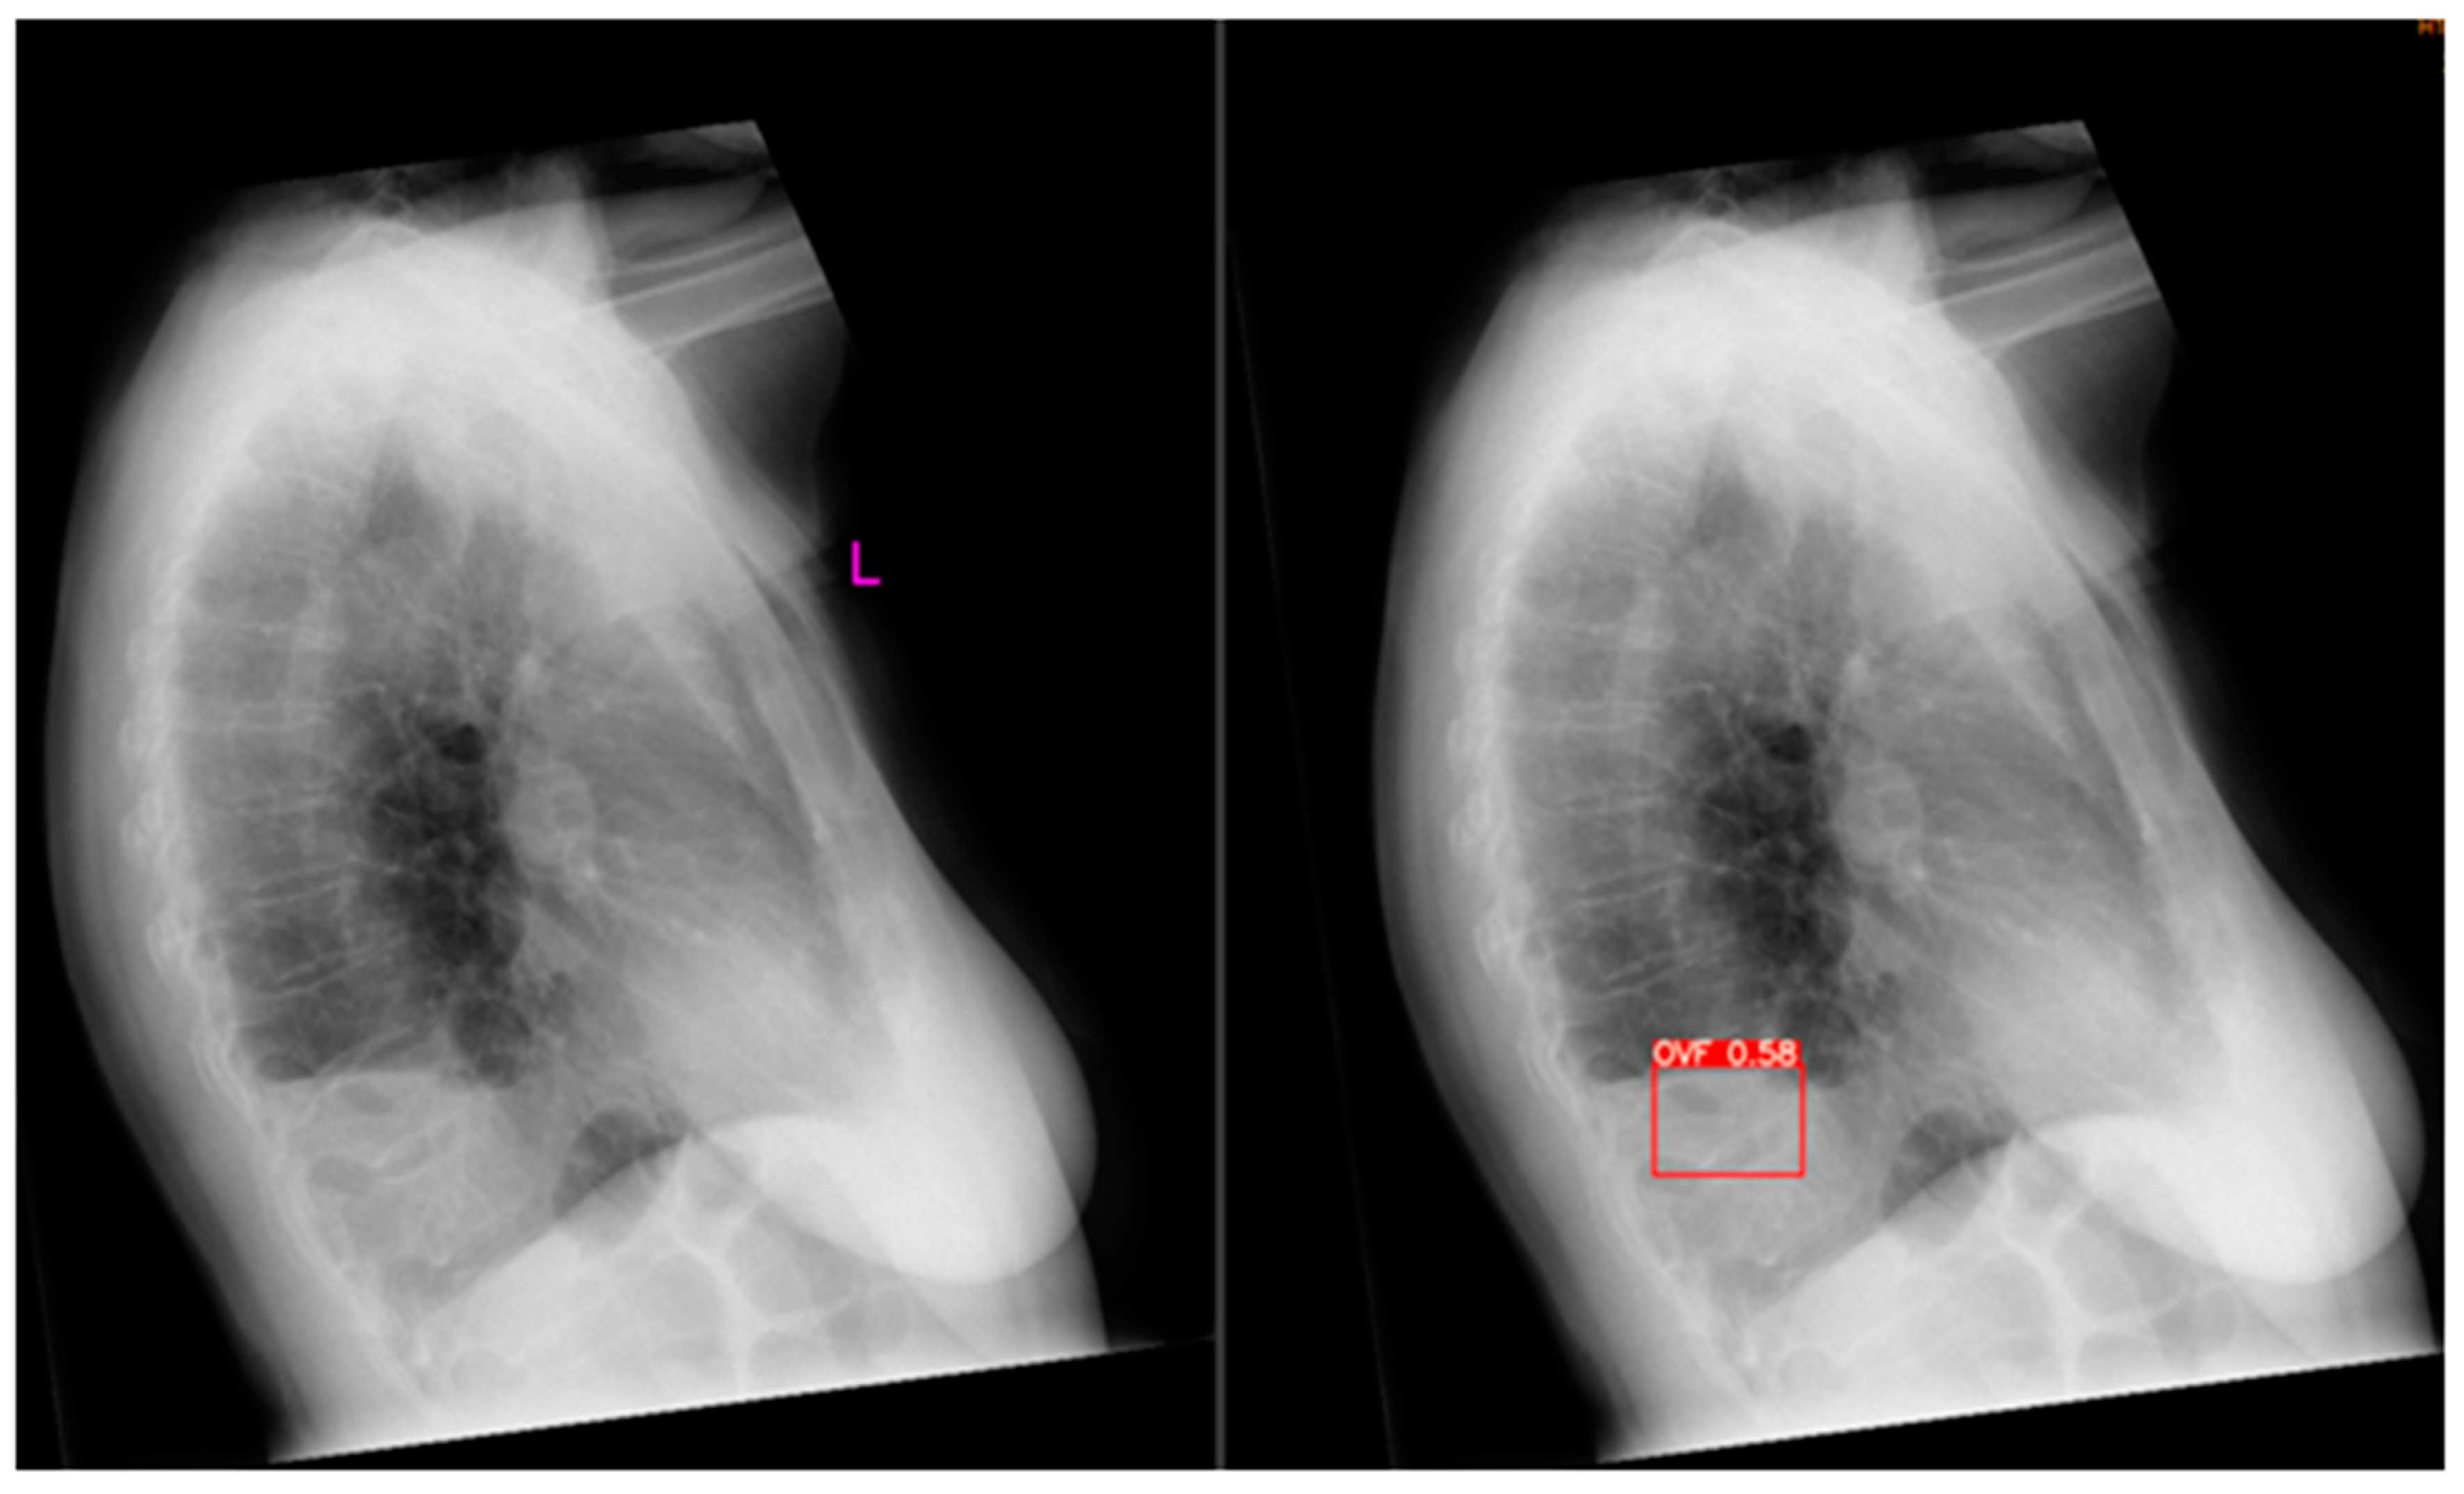

Figure 4. Example of a false-positive. Original radiograph is depicted on the left, Ofeye1.0 analysis with flagged OVF in red on the right. The radiologist did not classify this as an OVF. The total false positive rate was 5.1%.